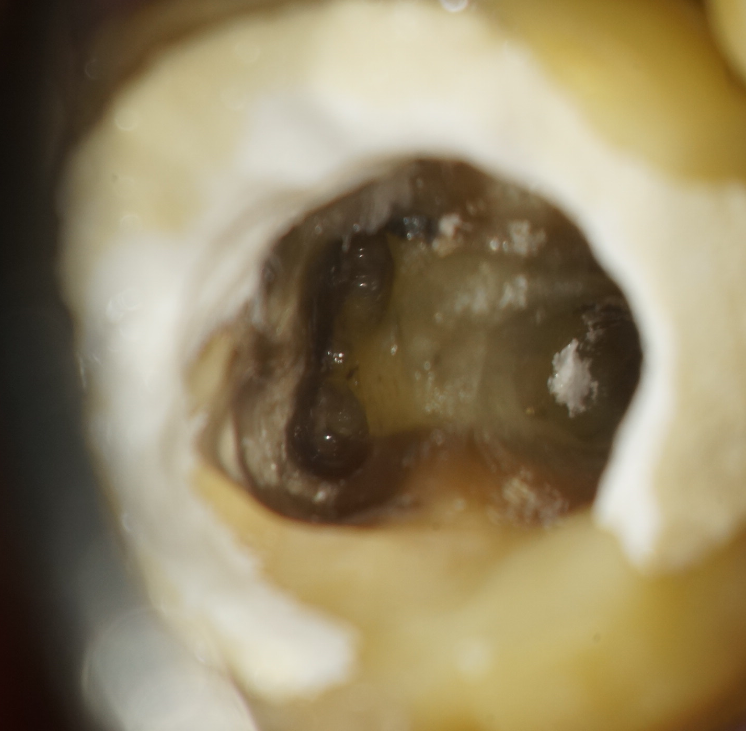

マイクロスコープ(顕微鏡)を使用した歯科治療によってこれまでとは格段に違う、精度の高い精密な治療が可能となりました。

今まで、歯科治療において手探りともいえる外科の歯科治療だと感じていました。それは、口の中とは見えそうでよく見えないところが多く、照明をあてたとしても暗くて、また狭く、陰に隠れてしまう部分が多いです。

実際に診に見えないところを、レントゲンを参考に想像しながら、経験と勘で治療していたといっても過言ではありません。 しかしマイクロスコープ(顕微鏡)を使うと確実に肉眼で見ながら治療できるようになり、とても精度の高い、成功率の高い歯科治療ができるようになります。

マイクロスコープ(顕微鏡)治療は特に、根の治療(根管治療)や歯根端切除、修復・充填、かぶせ(インレー・クラウン・ブリッジ)、抜歯等において私には欠かせない右腕となっています。